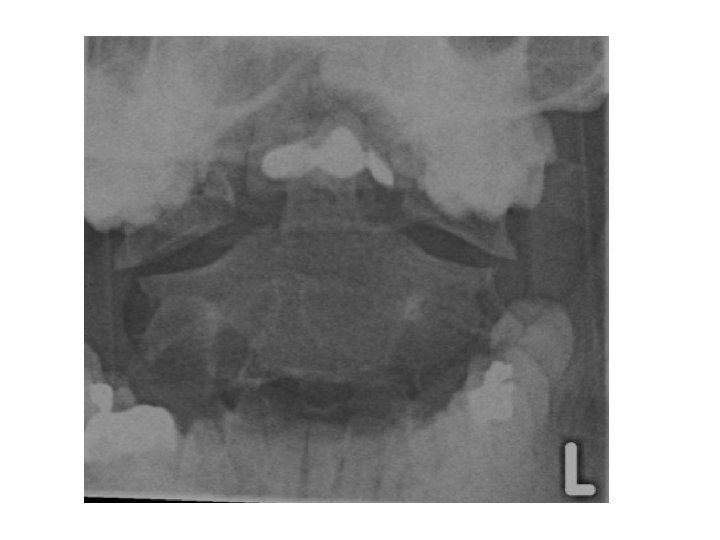

• Open mouth view • Adequate if entire Odontoid and lateral borders of C 1 and C 2 visible • Check : • lateral masses of C 1 must align with Odontoid • bilateral symmetry • Important also for Odontoid fractures